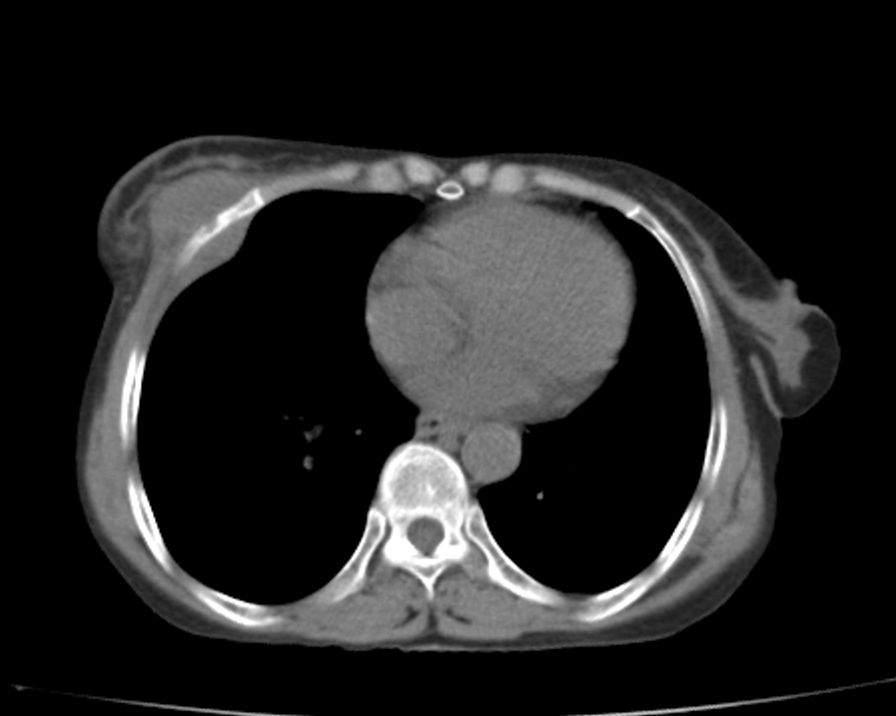

标题: CT21609:右乳包块1年,请各位讨论分析一下,乳腺CA, [打印本页]

标题: CT21609:右乳包块1年,请各位讨论分析一下,乳腺CA,

考虑---右乳癌并胸壁、肋骨、双肺转移。

考虑乳腺癌侵犯肋骨、胸壁及两肺转移可能性大。

右乳癌并胸壁、肋骨、双肺转移。

考虑右侧乳腺癌侵犯肋骨、胸壁及两肺转移。

支持考虑---右乳癌并胸壁、肋骨、双肺转移。

考虑右侧乳腺癌侵犯肋骨、胸壁及两肺转移可能。

考虑右侧乳癌并胸壁、肋骨及双肺多发性转移。